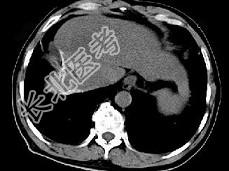

- 单项选择题女性患者,56岁, 腹胀、双下肢浮肿、乏力、食欲不振,影像所见如下图, 最佳的诊断是 ( )

A、肝炎后肝硬化并肝癌

B、局限性脂肪肝

C、原发性肝癌

D、血吸虫肝硬化并肝癌

E、酒精性肝硬化并肝血管瘤